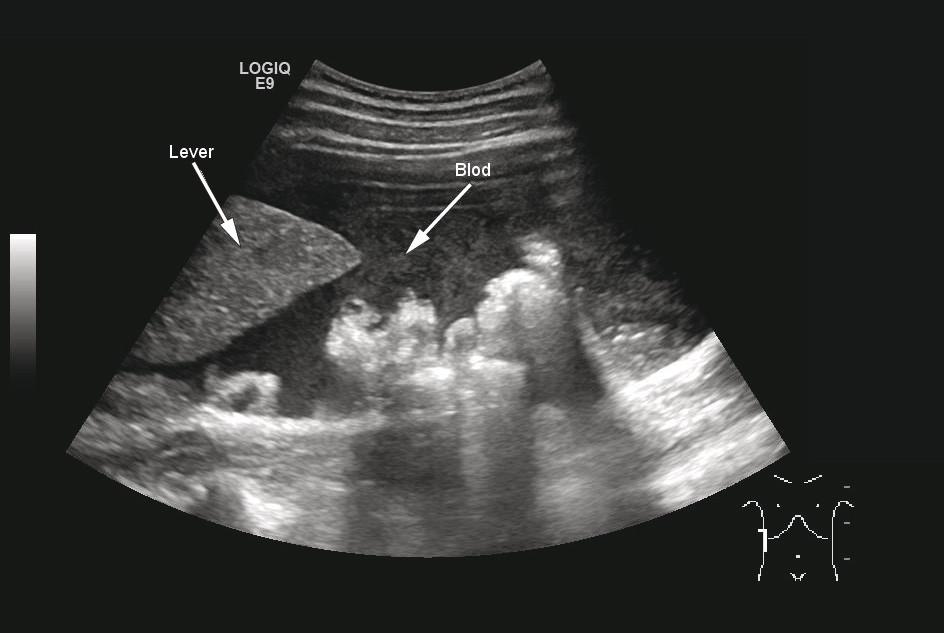

Blodprøver ved innkomst viste humant choriongonadotropin (HCG) i serum på 4 544 (0 – 4). Hemoglobin (Hb) var på 8,9 (11,7 – 15,3), og sank til 7,8 noen timer senere. I mellomtiden var det gitt vanlig intravenøs væskebehandling. Ultralyd abdomen viste «store mengder fri væske i buken med ekkomønster forenelig med blod» (fig 2) og «uregelmessig oppfylning på ca. 5 cm like kranialt for uterus, forenelig med ekstrauterin graviditet» (fig 3).